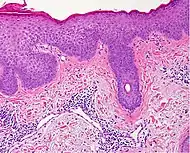

Prevesicular stage of bullous pemphigoid Image at right shows influx of inflammatory cells including eosinophils and neutrophils in the dermis (solid arrow) and blister cavity (dashed arrows), and deposition of fibrin (asterisks).[15] However, the diagnosis of bullous pemphigoid consist of at least 2 positive results out of 3 criteria:[19]

• Pruritus and/or predominant cutaneous blisters

• Linear IgG and/or C3c deposits (in an n- serrated pattern) by direct immunofluorescence microscopy (DIF)

• Positive epidermal side staining by indirect immunofluorescence microscopy on human salt-split skin (IIF SSS) on a serum sample.